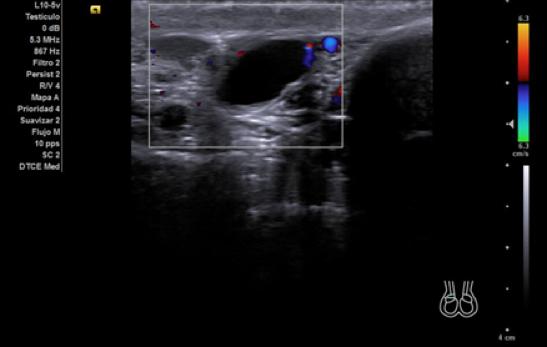

Hallazgos ecográficos

Ecografía Clinica: testículo izquierdo de tamaño y ecogenicidad normales, con microcalcificaciones y colas de cometa. Testículo derecho más pequeño que el contralateral, y en su zona central una lesión hipoecoica lobulada e irregular con captación intralesional y calcificaciones puntiformes en parénquima testicular. Con la sospecha de una neoplasia del testículo derecho se consulta con Urología, que solicita analítica y cita.

Los marcadores tumorales (LDH, BHCG, alfafetoproteína) son negativos y la ecografía se repite de forma reglada para descarte de neoplasia testicular. En esta última se define un teste derecho disminuido de tamaño y ecoestructura heterogénea, con áreas centrales hipoecogénicas aunque sin lesiones claramente definidas.

El diagnóstico de sospecha tras ser evaluado por Urología es una atrofia testicular derecha. En el diagnóstico diferencial se debe incluir la posibilidad de que la atrofia sea por una torsión testicular previa, una orquitis u orquiepididimitis que cause atrofia secundaria, traumatismos, infartos testiculares no traumáticos y neoplasia testicular. La ecografía clínica tiene parte de concordancia con la reglada, sin embargo, en esta última no se define la lesión hipoecoica lobulada e irregular que nos hace sospechar en AP que pueda tratarse de una lesión tumoral.